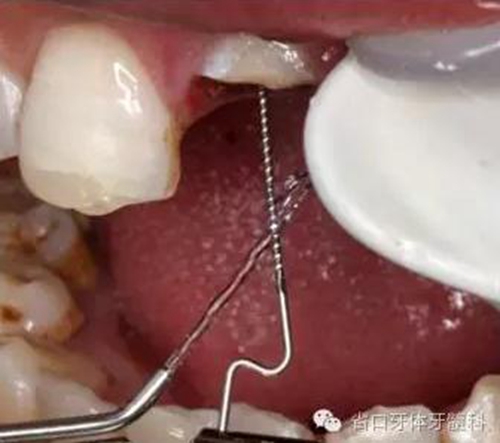

圖9. 腭側(cè)電刀切齦止血、暴露斷面,殘根斷面磷酸酸蝕